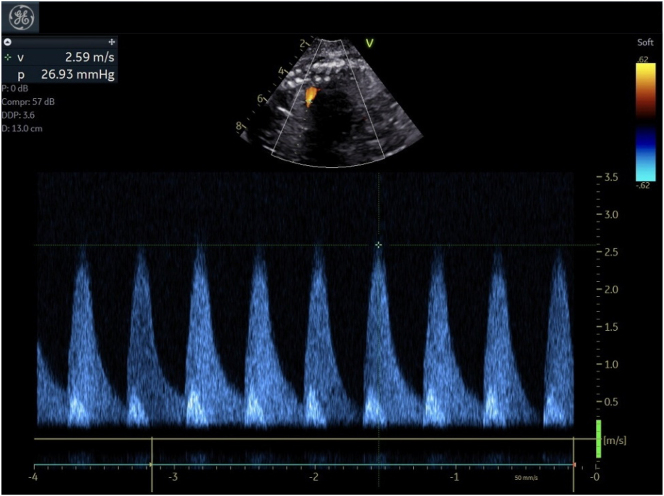

Case presentation: We describe a monochorionic diamniotic pregnancy complicated by twin anemia polycythemia sequence wherein the recipient twin developed signs of right heart failure secondary to premature ductus arteriosus constriction, requiring iatrogenic preterm delivery to avoid intrauterine demise.

Abstract Image